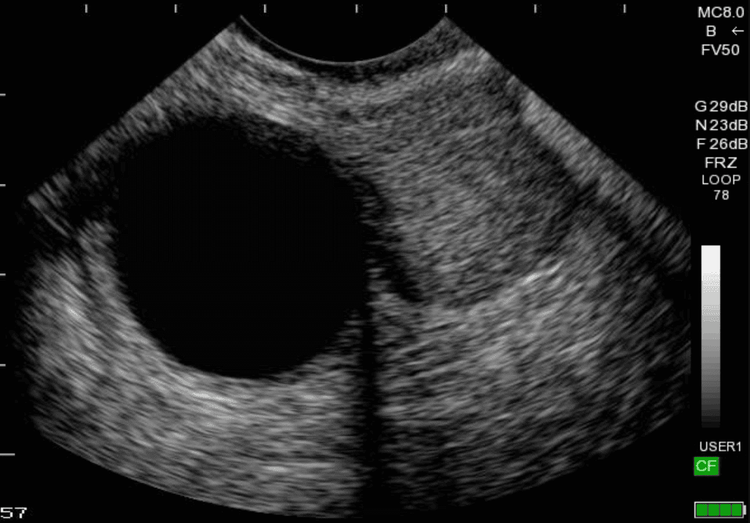

U nang buồng trứng được chẩn đoán qua siêu âm

• Nếu nghi ngờ ung thư buồng trứng dựa trên các triệu chứng bất thường, các xét nghiệm hình ảnh bụng và vùng tiểu khung được khuyến nghị như: siêu âm, chụp cắt lớp (CT) hoặc chụp cộng hưởng từ (MRI).

• Siêu âm tử cung buồng trứng qua đường âm đạo